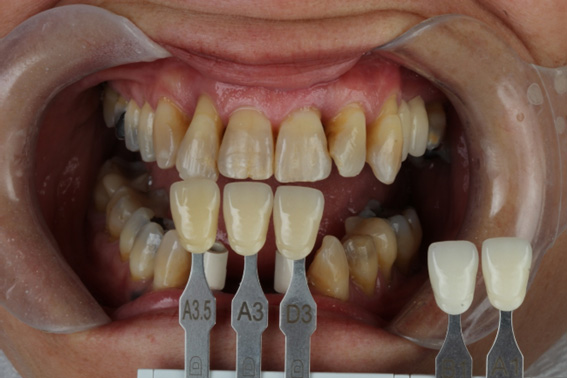

12 | Photography for shade selection and communication with the laboratory